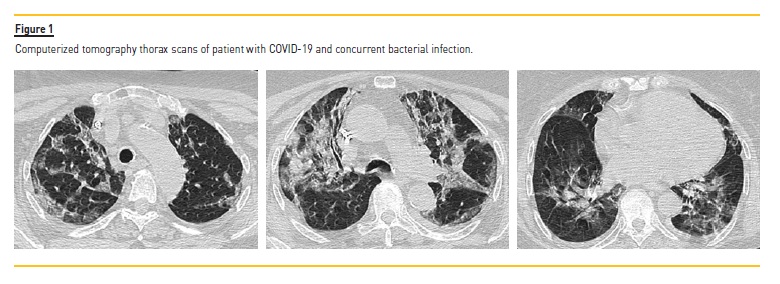

In this case, chest CT documented diffuse involvement by COVID 19 and aspects suggestive of bacterial infection (Figure 1).

Another patient developed global respiratory failure and therefore needed non‑invasive ventilation (NIV) for two periods, with good clinical response. No patient progressed to acute respiratory distress syndrome (ARDS), with the need of invasive ventilation and intensive care unit (ICU) stay.

In the few CT scans preformed, we could verify, in all patients, the presence of the typical ground‑glass opacities that are associated to the SARS‑C0V‑2 infection16. Gattioni et al, described two phenotypes of COVID‑19 pneumonia, the above‑mentioned lesions as the phenotype L, and the phenotype H as a kind of severe ARDS17. The latter wasn’t verified in our population. In fact, even our patient with the worst respiratory presentation, with type 2 IR and need for NIV, exhibited a type L phenotype.